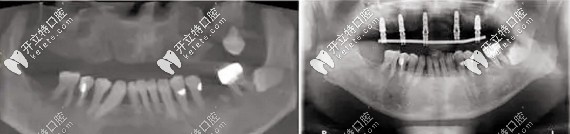

北京維樂(lè)種牙案例▼

北京維樂(lè)種牙案例